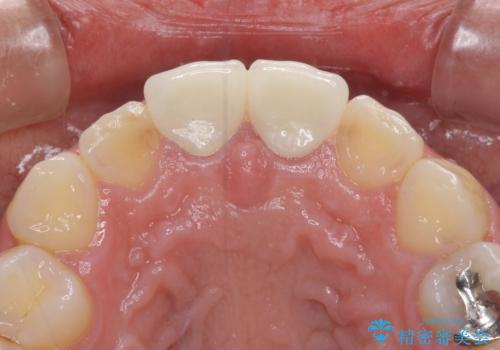

虫歯で神経を取り除いたことによる変色や充填物の着色などが認められたため、オールセラミッククラウンにて補綴することとしました。

また、咬耗により周囲の歯がすり減ったことで、前歯2本のみが長く見えていたため、周囲に長さを合わせることとしました。

治療を提供する側からすると、歯が短すぎるように思えますが、患者様としては長年気になっていた形態が改善され、大変満足していただきました。